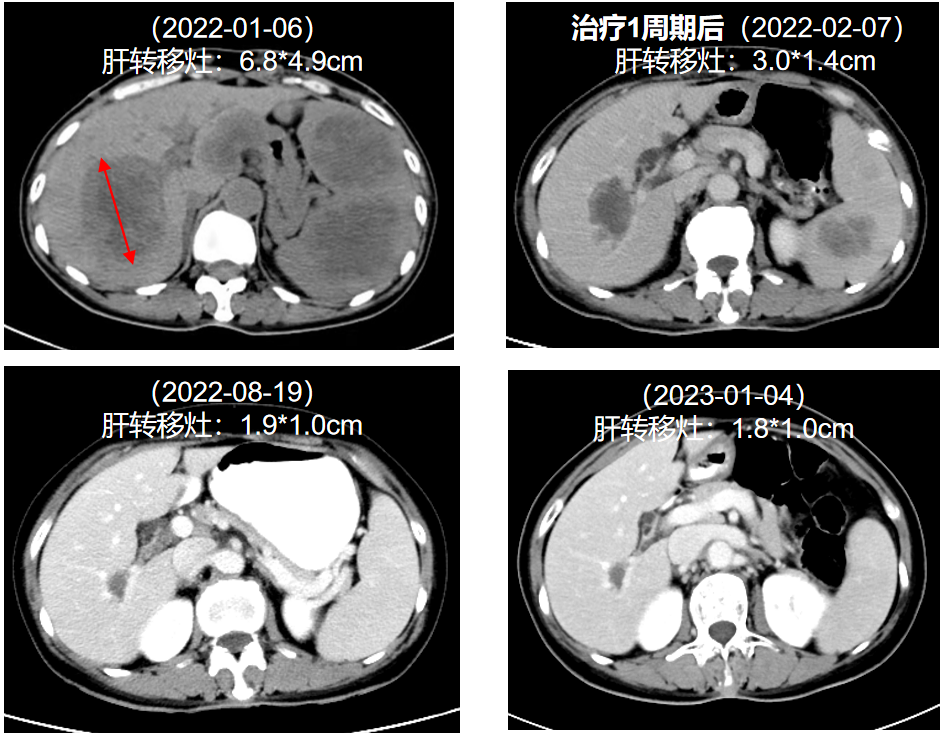

图2. 治疗前后肝转移灶变化

图片尺寸944x734